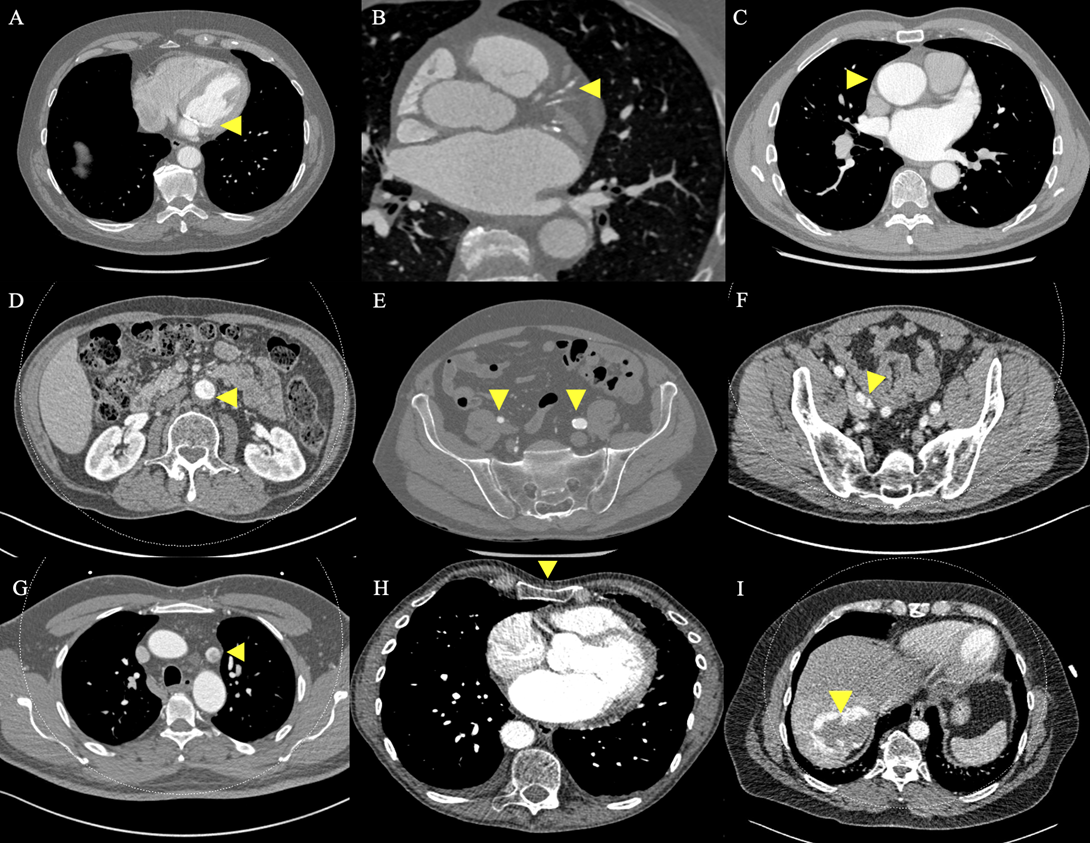

In total, 11 patients (13.9%) were excluded from MIMVS due to CT findings alone. CT exclusion criteria included: significant MAC (Figure 2A); significant coronary artery calcification (Figure 2B); dilatation of the ascending aorta to 4.4 cm (Figure 2C); significant mural thrombus in descending and abdominal aorta (Figure 2D); slender, calcified iliofemoral vessels (Figure 2E); dissection flap in the right external iliac artery (Figure 2F); incidental persistent left-sided superior vena cava (SVC) (Figure 2G); significant chest wall deformity (Figure 2H and 3A); incidental liver haemangioma (Figure 2I); 4.6 cm abdominal aortic aneurysm (AAA) (Figure 3B) and aberrant origin of the left circumflex artery (Figure 3C). A further 10 patients (12.7%) were excluded from MIMVS following multidisciplinary team (MDT) discussion due to: complexity of repair; non-isolated procedure and evidence of previous inferolateral myocardial infarction (MI). Additional CT findings resulting in modification of minimally invasive operative strategy included a partially bifid 4th rib (Figure 4A) and rib crowding (Figure 4B). Significant incidental findings that resulted in further investigation and referral to other pathways included a 10 mm lung nodule (Figure 5A) and 4 cm renal mass (Figure 5B).

Figure 2. Contraindications for minimally invasive mitral valve surgery (MIMVS). Preoperative CT revealing: A) Significant mitral annular calcification; B) Significant coronary artery calcification; C) Dilatation of the ascending aorta to 4.4 cm; D) Significant mural thrombus in the abdominal aorta; E) Slender, calcified iliofemoral vessels; F) Dissection flap in right external iliac artery; G) Incidental persistent left-sided superior vena cava; H) Significant pectus excavatum and I) Incidental liver haemangioma.

Patients with significant MAC are not considered optimal candidates for MIMVS.11 In our centre, the cardiac radiologist subjectively assesses MAC using CT. Moderate or severe MAC is considered to be significant. One patient was excluded from MIMVS due to significant MAC (Figure 2A). Identification, localisation and quantification of MAC is a relative strength of CT.11 The location and extent of MAC correlates with complexity of repair.11 Therefore, the choice of operative strategy will be dependent upon the surgeon’s experience. For surgeons at the start of the learning curve, MAC should be considered a contraindication for MIMVS. In addition to CT, preoperative TOE is a valuable imaging modality for the assessment of other valvular pathology and complexity of mitral valve dysfunction. A sternotomy is indicated for patients with complex valve disease and patients who require concomitant aortic valve surgery.

Significant coronary artery disease is a contraindication for MIMVS as patients will require concomitant coronary artery bypass grafting (CABG) via conventional sternotomy. Two patients were excluded from MIMVS due to significant coronary artery calcification (Figure 2B) that was initially picked up on CT and required referral for invasive coronary angiography. Both of these patients required concomitant CABG via sternotomy. The left circumflex artery (CxA) lies within close proximity to the posterior mitral valve annulus, this makes it susceptible to injury during MV surgery.12 Possible mechanisms of injury to the CxA include: direct laceration, occlusion with a suture, distortion due to tissue retraction, spasm and external compression by the annuloplasty ring.11 Injury to the CxA during MV surgery is a rare complication, recent studies have reported an incidence of 0.3% to 0.5%.12,13 However, injury to the CxA can lead to MI and is associated with a considerable risk of mortality.12 Therefore, it is important to measure the distance between the mitral annulus and the left CxA using preoperative CT in order to reduce the potential risk of injury occurring. In our study, the closest distance between the left CxA and MV annulus was 2 mm (Table 2) and there were no reported injuries to the CxA during MIMVS. Technical aspects such as careful placement of annular sutures and avoiding large quadrangular leaflet resections may help to prevent injury and should be considered when planning MIMVS.13 Additionally, one patient was excluded from MIMVS due to aberrant origin of the left CxA (Figure 3C). Aberrant origin of the left CxA is associated with an increased risk of mechanical coronary occlusion and patients may require a concomitant myocardial revascularisation procedure.14

CPB with retrograde perfusion is established by cannulation of the femoral artery and vein and occlusion of the ascending aorta with an endo-aortic balloon or cross-clamp.11 In our centre, we use transthoracic external aortic cross-clamping (TTC) to occlude the ascending aorta. CPB with retrograde perfusion and cross-clamping are associated with an increased risk of aortic dissection, retrograde embolization and stroke.15 CT allows for visualisation and assessment of the great vessels of the heart. The ascending aorta is screened for significant atherosclerotic burden in order to assess suitability for CPB and TTC. The identification and quantification of atherosclerotic changes in vessel walls is a relative strength of CT.11 It is also important to measure the diameter of the ascending aorta as dilatation increases the risk of aortic dissection and rupture.16 Dilatation of more than 4 cm is a contraindication for MIMVS.2 One patient was excluded from MIMVS due to dilatation of the ascending aorta to 4.4 cm (Figure 2C). There have been no reported cases of aortic dissection during MIMVS in our centre. Aortic elongation has previously been reported as a potential risk factor for Type A aortic dissection and is considered to be a relative contraindication for MIMVS.17 Currently, we do not screen for aortic elongation as part of our preoperative CT workup for MIMVS. However, it is recommended that aortic elongation is evaluated during preoperative planning in order to prevent potentially avoidable complications. CT also revealed an incidental persistent left-sided SVC (Figure 2G). The patient was excluded from MIMVS due to the potential risk of impaired venous drainage which may have led to excess blood in the operative field.

CT is also used to assess suitability of the aortoiliofemoral vasculature for cannulation and CPB in order to reduce the potential risk of dissection, embolization and stroke.15 In the absence of significant vascular disease, femoral arterial cannulation is the method of choice in our centre. Significant aortoiliofemoral thrombus, calcification, aneurysmal disease, tortuosity and evidence of dissection are all contraindications for femoral arterial cannulation.18 Slender iliofemoral vessels with a luminal diameter of less than 6 mm are also unsuitable for cannulation.2 Slender and/or calcified iliofemoral vessels (Figure 2E) resulted in the exclusion of two patients from MIMVS. One patient was excluded from MIMVS as they were found to have a dissection flap in the right external iliac artery (Figure 2F) and a tortuous left femoral artery. Another patient was excluded due to the presence of a 4.6 cm AAA (Figure 3B) and significant mural thrombus in the descending and abdominal aorta (Figure 2D). One other patient was found to have a 3.1 cm AAA but was deemed suitable for MIMVS as the aorta was only mildly dilated and there was a low risk of rupture. A sternotomy with antegrade perfusion is considered a safer approach for patients with significant aortic or iliofemoral disease.7 A recent meta-analysis of data from 57 studies (13,731 patients) demonstrated that preoperative CT for MIMVS is associated with a reduced risk of perioperative stroke (1.5%) and a trend towards lower operative mortality (0.8%).19 In our present study, the 30-day mortality and stroke rates for MIMVS were 0.0% and 1.8% respectively. Comprehensive preoperative CT evaluation for MIMVS may help reduce the potential risk of mortality and stroke as it allows for individualisation of the surgical approach and exclusion of patients with significant vascular disease.

Three-dimensional CT reconstructions of the thorax allow for assessment of chest wall anatomy and visualisation of the operating field in order to aid preoperative planning, reduce operative times and prevent potentially avoidable complications. Preoperative understanding of patient anatomy is particularly important in minimally invasive surgery as exposure is limited.2 In our experience, we have found that CT and 3D CT reconstructions are useful tools for accurately determining the optimal ICS for right-sided minithoracotomy incision based upon the position of the left atrium, pulmonary vessels and right hemi-diaphragm. The fourth ICS is the optimal incision point in 65.8% of patients (Table 2). We also use CT and 3D CT reconstructions to assess chest wall deformity. Significant chest wall deformity may be a contraindication for MIMVS depending upon the surgeon’s experience. One patient was considered unsuitable for MIMVS due to significant pectus excavatum (Figures 2H and 3A) that may have caused difficulty with surgical approach. Other patients required modification of minimally invasive operative strategy due to rib crowding (Figure 4A) and a partially bifid 4th rib (Figure 4B). CT and 3D CT reconstructions are also used to visualise aberrant vessel anatomy (Figure 3C) and subjectively assess iliofemoral tortuosity in order to aid preoperative procedural planning and prevent potentially avoidable complications.2 Additionally, preoperative CT may highlight incidental extra-cardiac findings that may exclude the patient from MIMVS (Figure 2I) or require further investigation and referral to additional pathways (Figures 5A and 5B).